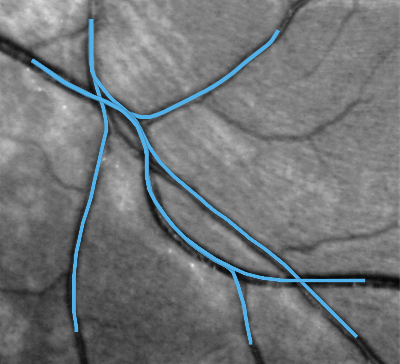

В частности, задача поиска выделяющихся кривых возникает в анализе медицинских изображений при поиске кровеносных сосудов на фото сетчатки глаза человека, см. Рис. 3. Типичные проблемы для промышленных систем трассировки возникают в ситуациях, когда сосуды на фото пересекаются. Решение этой проблемы достигается путем поднятия изображения в расширенное пространство позиций и направлений. Метод трассировки сосудов с помощью СР кратчайших на предложен в [11].

Недостатком СР модели является наличие точек возврата. Такие кривые нежелательны в задаче трассировки сосудов. Ограничение управления на полукруг устраняет этот недостаток. При этом точки возврата становятся точками поворота на месте. Возникновение точки поворота типично наблюдается в местах ветвления сосудов. Более подробно с результатами трассировки сосудов с помощью оптимальных траекторий на с управлением в полукруге можно ознакомиться в [28].